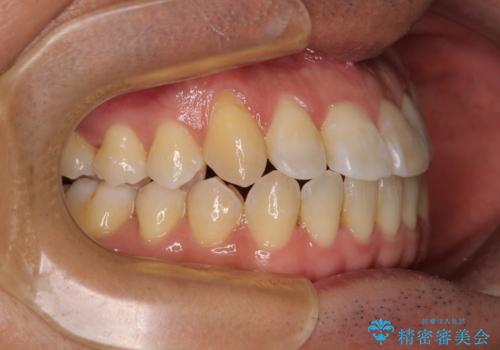

左右の八重歯が気になる ワイヤー装置での咬み合わせ改善

- 八重歯と前歯のデコボコを気にして来院された患者様です。

営業職であり、商談などで飲食をする機会が多いとのことで、インビザラインではなく、ワイヤー装置にて矯正治療を行うこととしました。

舌の突出癖がなかなか改善されず、上下前歯部の接触が得られるまでに予定の倍ほどの期間がかかりました。